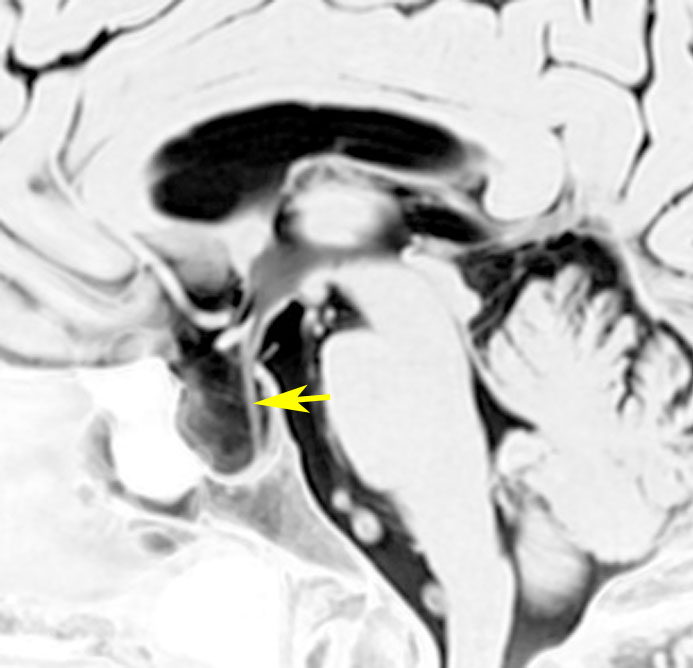

トルコ鞍内くも膜のう胞:先天性無症候性

偶然に発見されたものです,下垂体柄(黄色の矢印)がすごく伸びていて下垂体組織が扁平化していますが,先天性と思われ無症状です。何も治療しないでほっておきます。